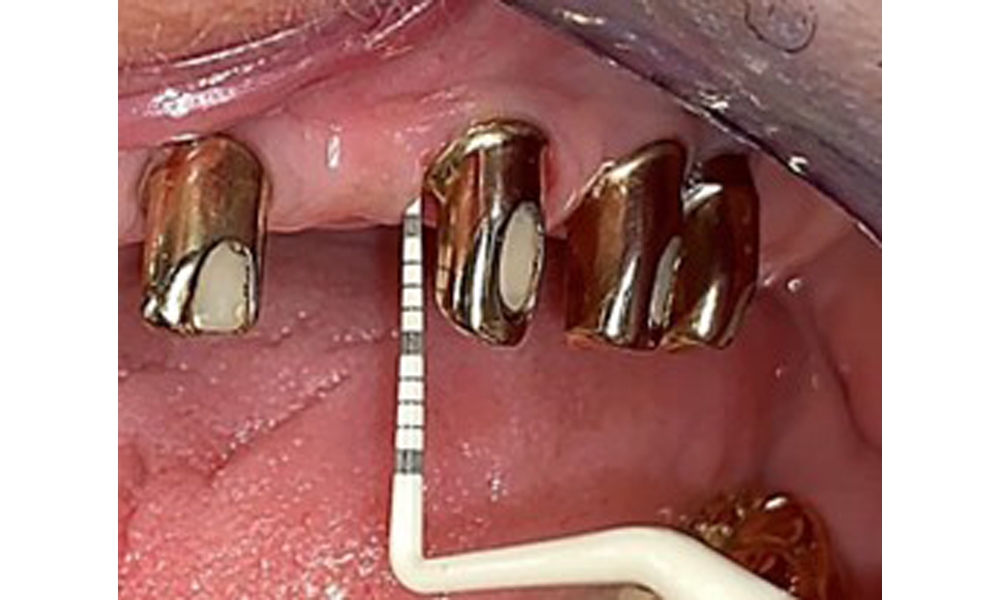

На пациентката е поставена комбинирана подвижна горночелюстна телескопична протеза преди повече от 25 години (фиг. 1, фиг. 2, фиг. 3) и тя е много доволна от протезите си. Пациентката има адекватна фиксирана протеза за долната челюст (фиг. 4).

Денталните открития са следните: Комбинирани снемаеми протези на импланти и телескопични протези, поддържани от зъби, на импланти 15, 13, 21, 23, 24, 25 и зъб 11 (фиг. 1, фиг. 2, фиг. 3). Пациентът е снабден с фиксирана долночелюстна протеза. Над зъби 37-34 и 45-47 бяха налични адекватни мостове (фиг. 4), краищата на коронките бяха интактни и нямаше активен кариес. Върху зъб 43 имаше композитна пломба с маргинална празнина. Имаше рецесия на долната гингива, която разкриваше от 1 до 3 mm от кореновата повърхност. Това се отнася и за 11.